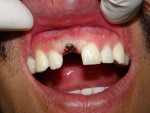

Immediate Molar Implant